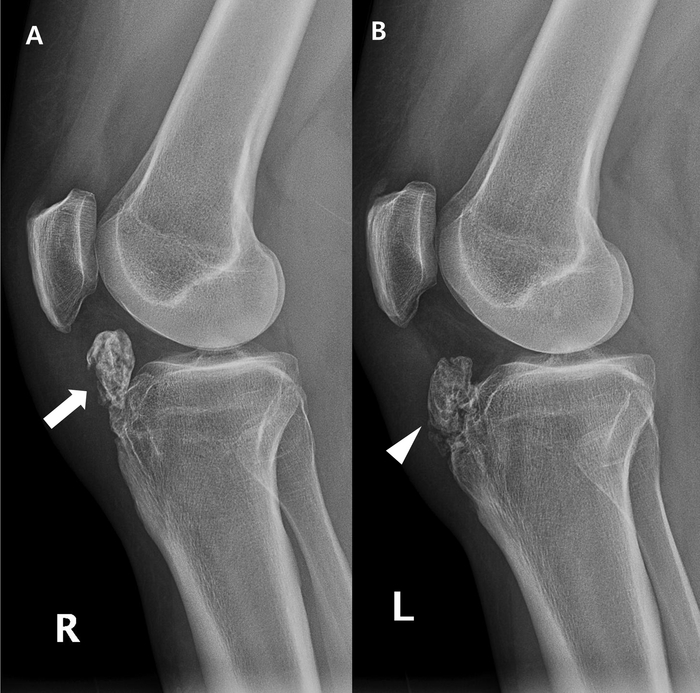

На снимках 2 разных стадии болезни Шляттера: слева с отрывом бугристости большеберцовой кости, справа -без.

От состояния кости строиться тактика лечения и прогноз.

Я повожу осмотр коленного сустава, вокруг него. Вместе с пациентом проводим ряд тестов. Обычно для постановки диагноза достаточно знать где болит, как болт и провести осмотр. Но бывают состояния, когда нужно уточнить степень заболевания. Тогда направляю на рентген коленного сустава в 2-х проекциях.